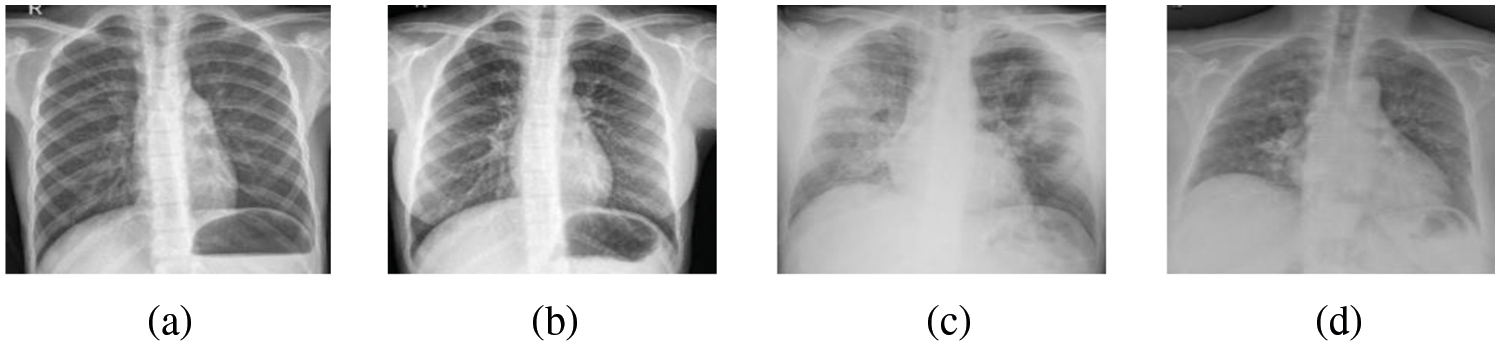

The representative feature of the chest X-ray images of COVID-19 in Fig. 2 is large blurred lungs, possibly with cleft thickening at night and a small amount of pleural effusion. When the patient gets worse, there is a shadow of diffuse consolidation in both lungs and white lungs may appear, sometimes accompanied by pleural effusion.

Figure 2: [8] (a) (b) is the X-ray image of normal people, (c) (d) is the X-ray image of COVID-19 patients. Images (c) (d) represent blurred lungs with a shadow of diffuse consolidation compared with those of normal people